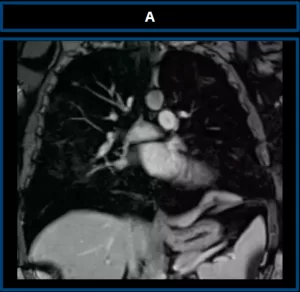

Chest MRI

Axial MRI images in T1-weighted (A), T2-weighted with fat suppression (B), DWI (C), and ADC (D) sequences demonstrate a lesion with elongated/discoid morphology, centered at the base of the left hemithorax (yellow arrows), demonstrating isointense signal on T1, mildly hypointense signal on T2, and no diffusion restriction.

Pre-contrast (A) and post-contrast T1-weighted sequences in the arterial (B), portal venous (C), and delayed (D) phases, all with fat suppression, demonstrate slow and progressive enhancement after contrast administration (yellow arrows).